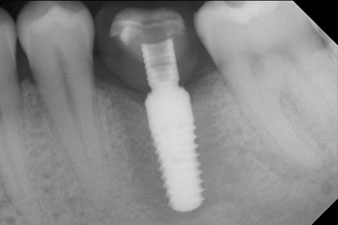

Последните снимки показват закрепената с винт монолитна композитна корона на място и рентгеновата проверка (фиг. 9 и 10) (6).